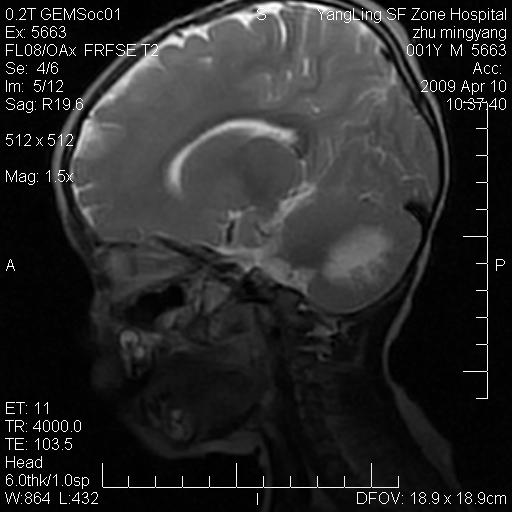

患者:1岁半,两天前外伤收住我院,ct检查小脑占位

考虑星形细胞瘤,建议增强

髓母细胞瘤或血管母细胞瘤,增强后可以鉴别;影像资料见 <。鱼博浪老师的《中枢神经系统ct与mr鉴别诊断》 小脑部肿瘤章节。

髓母细胞瘤或血管母细胞瘤!支持!

支持考虑髓母细胞瘤

考虑----髓母细胞瘤可能性大

考虑髓母细胞瘤或室管膜瘤。

支持髓母细胞瘤。

考虑髓母细胞瘤。

考虑髓母细胞瘤或星形细胞瘤

考虑髓母细胞瘤.

考虑髓母细胞瘤可能性大。

小脑肿瘤.考虑髓母细胞瘤可能.

就病灶部位及临床资料首先考虑髓母.